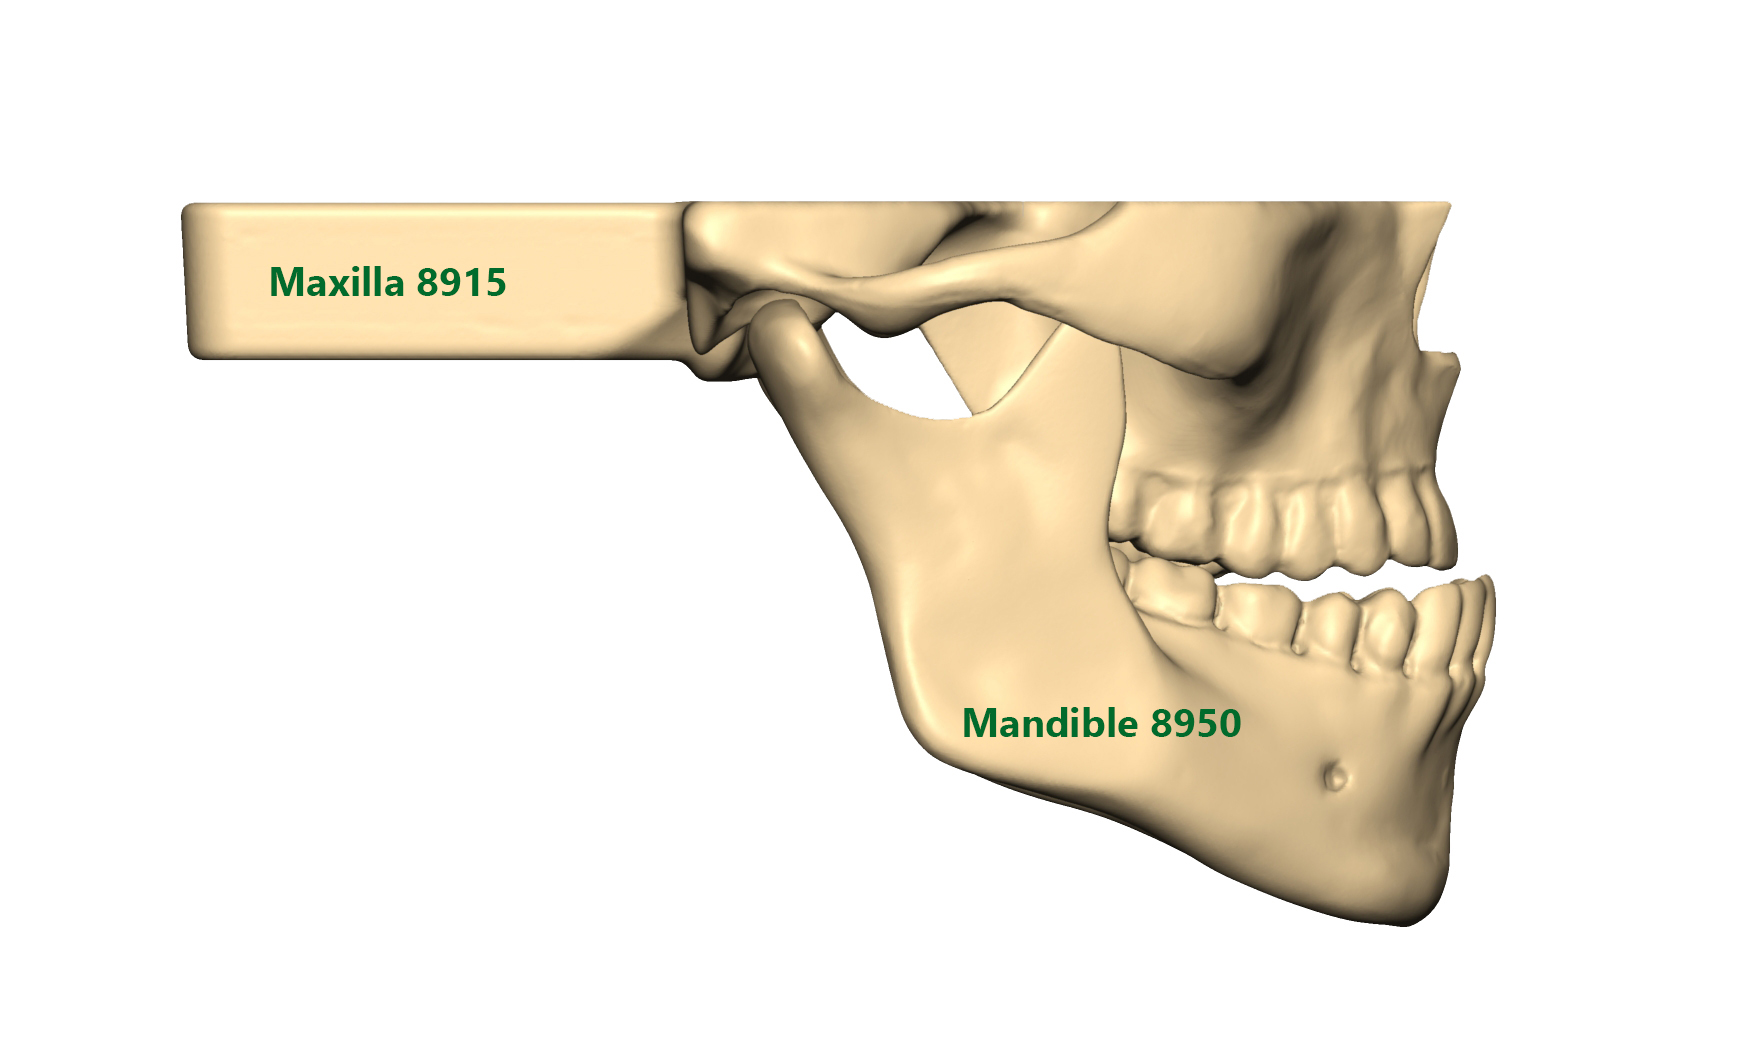

Mandible and Maxilla models with Easy Clip

SYNBONE’s new Mandible and Maxilla models with easy clip mechanism offer the highest flexibility when combining the products together. The Mandibles do also correspond to our 8200 / 8700 and 8800 Skull models.

You can choose from standard, overbite or underbite situations for your orthognathic surgery education. We offer intact, fractured or prefractured models for your LeFort I and BSSO workshops. Thanks to the drill holes between each tooth all models can be used for cerclage wiring.

Our Maxillas with Easy Clip mechanism correspond to the 8900 and 8950 Mandible series. Rubber brackets allow a firm hold of the mandibles.

All Mandibles with Easy Clip mechanism correspond to our 8200 / 8700 and 8800 Skull models as well as 8910 and 8915 Maxillas.

Reusable cerclage wiring alternative clip for Maxilla/Skull and Mandible fixation. Also ask for our regular / overbite and underbite OP-Splints.